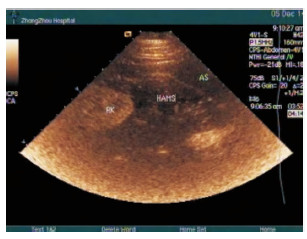

1.3 超声表现床旁US联合CEUS检查30例患者,诊断的16例腹膜后血肿,8例腹膜后血肿位于肾脏周边,6例位于骨盆内,2例位于左上腹部,最大180 mm×78 mm,最小40 mm×38 mm。

常规超声图像表现:根据位置不同,血肿表现为椭圆形或不规则形低回声或混合回声区,内回声紊乱,边界欠清晰,彩色多普勒示其内未见彩色血流信号,未能判断出有无活动性出血。

CEUS表现:注入造影剂后,腹腔脏器及腹膜结构开始显影,病灶区域位于增强的腹膜结构(图 1、2)后方,始终未见造影剂进入。造影后血肿区边界范围显示更清晰,其中3例肾周血肿的病例(图3),在注入造影剂后可见造影剂自受损的肾被膜处呈“喷泉样”向肾周溢出,诊断活动性出血,以上3例均得以手术证实,出血部位判断准确。

| 图 1 右下腹髂腰肌前方的腹膜后血肿,腹膜结构 |

| 图 2 肾周血肿及腹膜结构(箭头处) |